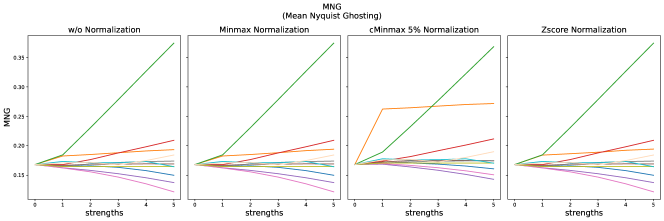

4.2 Non-Reference Metrics

The results for all strengths are given in Fig. A.5. For the maximum strength (s=5), the results are summarized in Tab. 9 without normalization and for cMinMax normalization.

Minmax normalization and Zscore normalization do not have any effect on the selected non-reference metrics, therefore these results are not shown here.

For the BLUR metric, scores clearly increase for blurred images, but also clearly decrease compared to the reference for stripe artifacts, Gaussian noise and the gamma transform for . For small strengths of translation and elastic deformation slightly increased blurriness is measured, but drops again for strengths > 3.

Compared to the reference images, MNG strongly drops for images with stripe artifacts. With cMinMax normalization, MNG also detects ghosting.

MSN decreased most strongly for stripe artifacts, Gaussian noise and ghosting. The difference for higher distortion strengths is only small, while the lowest distortions are already detected.

The non-reference metrics can give valuably additional information about the quality of synthesized images. Blurring is easily and reliably detected by the BLUR metric. However, assessed blurriness decreases with other distortions, such as Gaussian noise, stripe artifacts or gamma transforms, when these increase image contrast.

The MSN metrics represents the line-wise correlation between neighboring lines. The reference value in our experiments lies at 96%, which is probably caused by high anatomical consistency in the present pixel spacing. It strongly decreases for stripe artifacts, which fits to the fact, that the stripes change relations between local image intensities and are not oriented along the x- or y-axis. Random Gaussian noise, reduces statistical correlation and thereby also MSN. Ghosting also reduces MSN, as it additionally distorts image intensities locally.

The MNG metric only slightly increases with ghosting. One reason could be the relative weak scaling of the ghost intensity in our experiments. In contrast, stripe artifacts significantly increased the MNG metrics. Compared to MSN, by coincidence, stripes seem to be in the same phase at the half-image width distance and thereby drastically increase line-wise correlation.